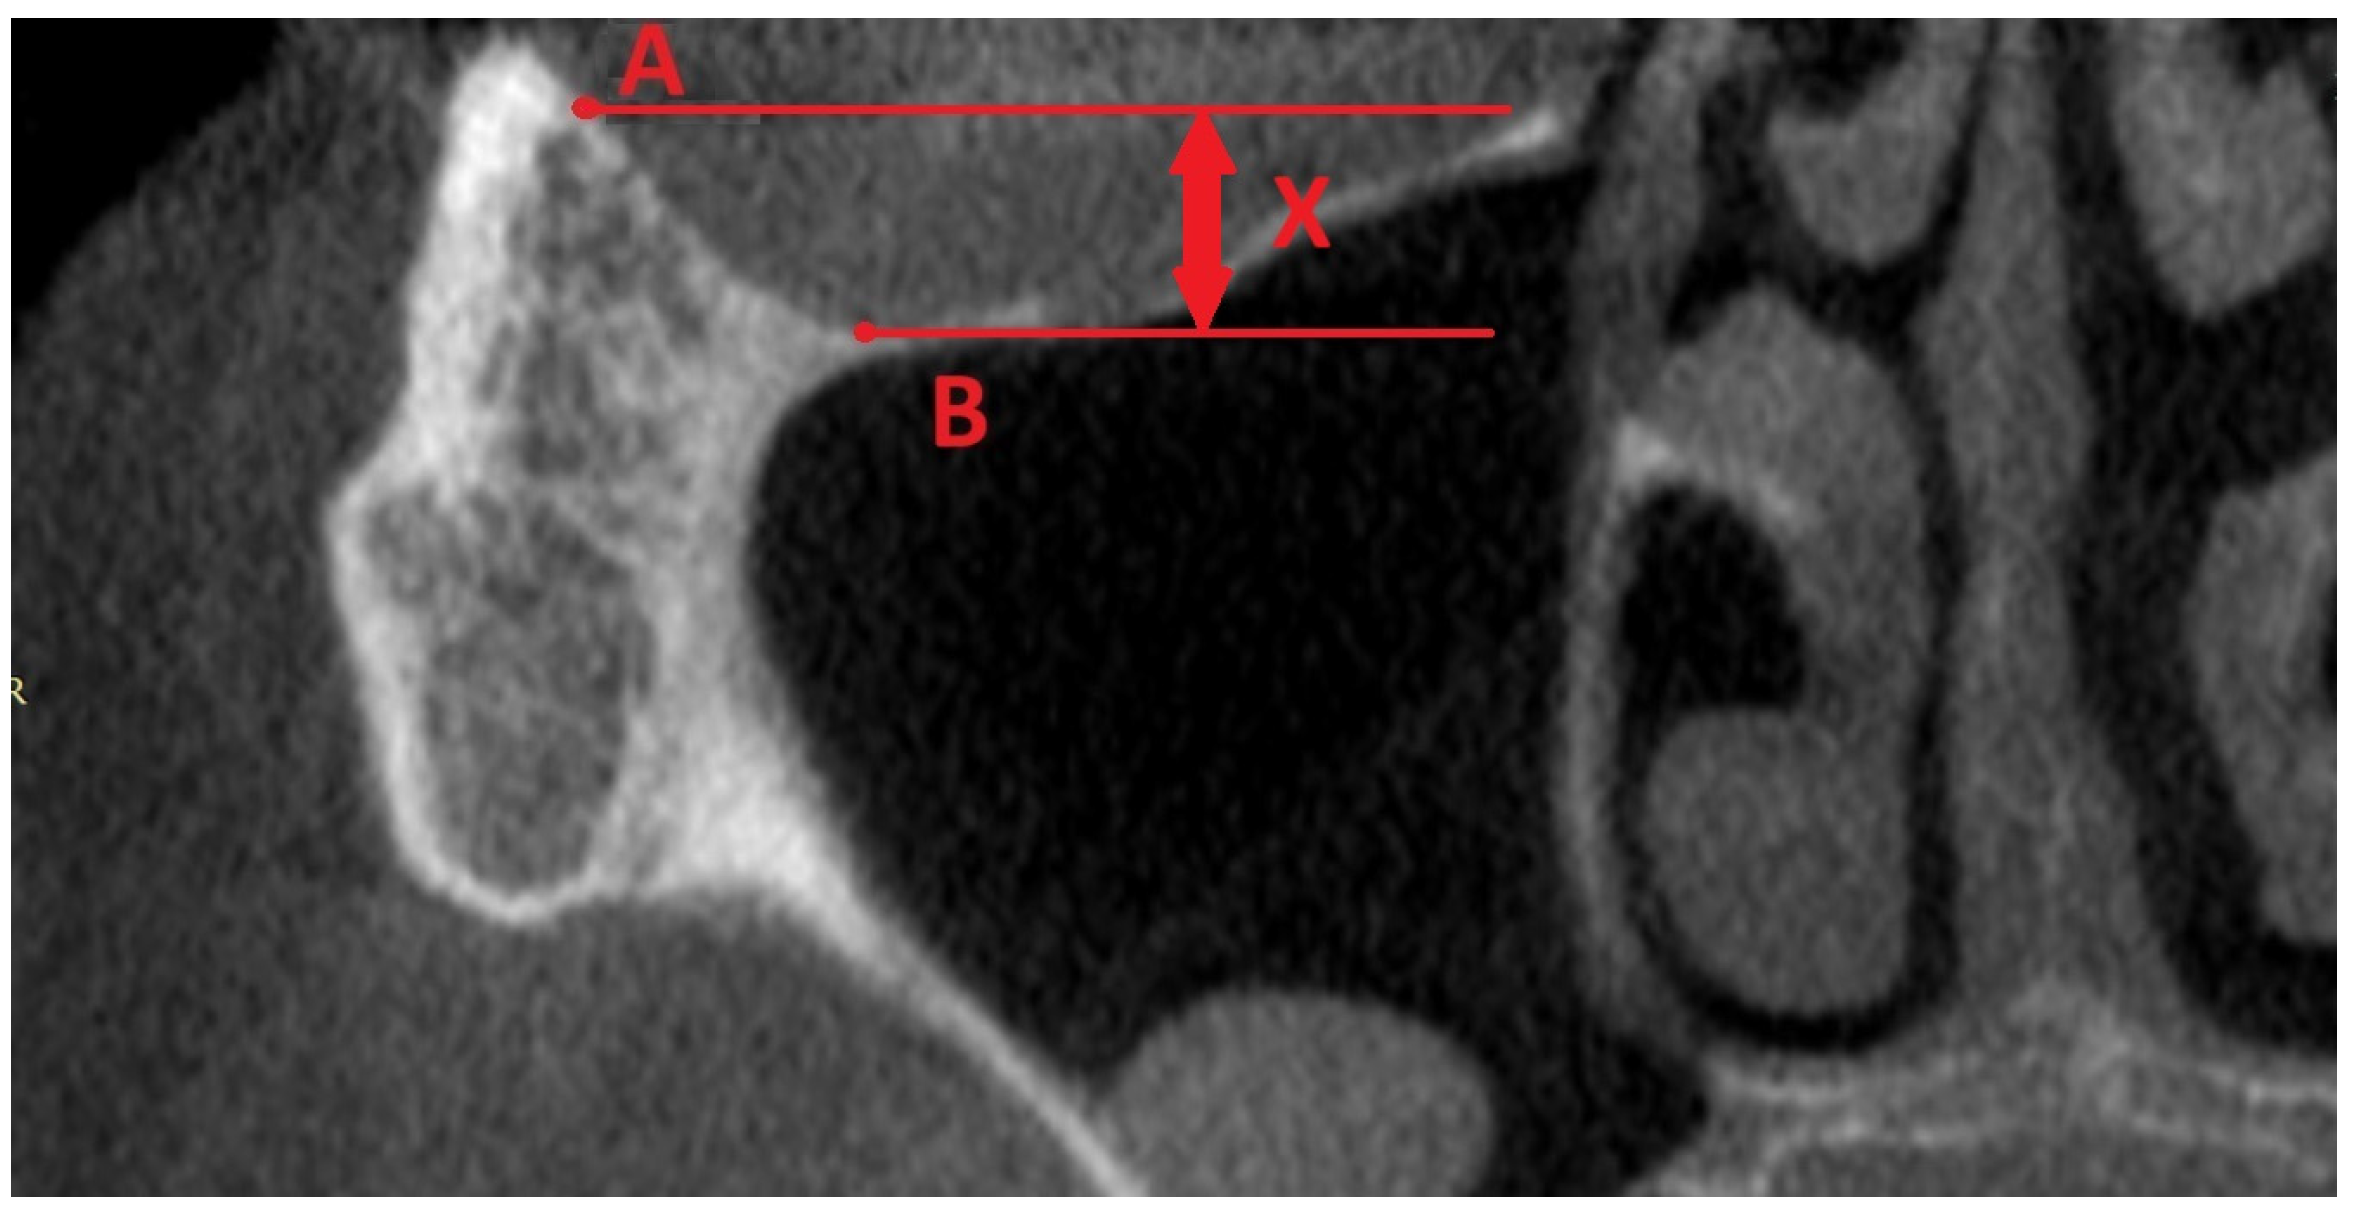

3.3. ZOF

4.4. Zygomatic Orbital Floor (ZOF)